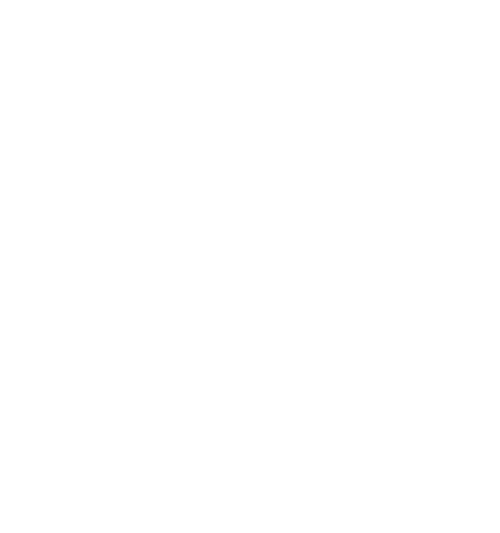

Spezialdiagnostik bei Moyamoya und atherosklerotischen oder ungeklärten (idiopathischen) Gefäßverschlüssen

Um die richtigen Therapieentscheidungen treffen zu können, bedarf es einer ausführlichen diagnostischen Abklärung. Diese geht weit über die routinemäßig durchgeführten Untersuchungen hinaus und ist nur an einem Spezialzentrum mit ausreichend Expertise verfügbar. Durch unsere jahrelange klinische Erfahrung und Forschungsaktivitäten haben wir standardisierte diagnostische Abläufe für alle Patientinnen und Patienten definiert, um dann die therapeutische Strategie festzulegen.

So stellen wir sicher, dass nur die Patienten / Gefäßterritorien revaskularisiert werden (einen Bypass bekommen), die dies auch wirklich benötigen. Gleiches gilt auch für die Nachsorge nach operativer Bypassanlage, sowie alle Verlaufskontrollen bei konservativem Vorgehen ohne Bypassoperation.

Cerebrale Angiographie

Die konventionelle cerebrale Angiographie ist die wichtigste Untersuchung zur Diagnosestellung der Moyamoya Krankheit. Diese Untersuchung ist zu vergleichen mit einer Herzkatheteruntersuchung, eben nur mit Darstellung der Hirnarterien. Bei Moyamoya-Patientinnen und Patienten werden, im Gegensatz zu Routineuntersuchungen bei anderen cerebralen Erkrankungen, selektiv die vordere und hintere Zirkulation des Gehirns dargestellt, sowie auch die Versorgung der extrakranialen Gefäße. Diese umfassende Darstellung ist besonders wichtig, um die vollständige Ausdehnung der Erkrankung zu erfassen und alle möglicherweise veränderten Blutflüsse im Gehirn zu verstehen. Je nach Befund werden die Engstellen der Hirnarterien, sowie auch mögliche begleitende Veränderungen selektiv hochauflösend dreidimensional dargestellt. Es ist wichtig zu erwähnen, dass die Moyamoya Krankheit nicht über eine Katheterintervention (Ballonaufweitung der Engstelle) behandelt werden kann und darf. Dies haben mehrere Studien gezeigt.

Funktionelles MRT (breath-hold fMRI)

In der konventionellen Angiographie und im konventionellen MRT können selektiv die Gefäße, der Blutfluss, und das Gewebe gut dargestellt werden. Diese Untersuchungen erbringen jedoch keine Aussage über den absoluten Blutfluss im Gehirn. Adaptierte Untersuchungen des MRTs, sowie auch des CTs zur Messung der Hirndurchblutung (Perfusion) haben sich in der Vergangenheit bei Moyamoya Betroffenen auf Grund der Kollateralen als zu wenig sensitiv gezeigt, um die Durchblutung zuverlässig darzustellen.

Durch die Erforschung und Weiterentwicklung des funktionellen MRTs haben wir eine Untersuchung etabliert, welche die Reaktivität der Hirngefäße (und somit indirekt die cerebrale Durchblutungsreserve) darstellen kann. Beim sogenannten "breathhold", also Atemanhalte-fMRT müssen die Patientinnen und Patienten in mehreren Zyklen für jeweils wenige Sekunden die Luft anhalten. Dadurch erhöht sich die CO2-Konzentration im Blut und die Hirngefäße stellen sich weiter. Diese Veränderung des Blutflusses kann dann indirekt gemessen werden. Da es sich hierbei um eine sehr neue Methode handelt, ist zu erwähnen, dass medizinische Entscheidungen primär ausschließlich in Zusammenschau aller Befunde und bei jeglicher Unschlüssigkeit mit dem ergänzenden PET/CT getroffen werden. Das fMRT hat sich jedoch als exzellentes Screening-Tool und für die langfristigen Nachkontrollen erwiesen.

H2 15O PET CT

Die wichtigste Untersuchung zur absoluten Darstellung des Blutflusses im Gehirn im Ruhezustand (baseline) und nach medikamentös stimulierter Gefäßweitstellung ("Diamox/Acetazolamid-Challenge") ist das sogenannte Wasser (H2 15O) PET/CT. Bei dieser Untersuchung wird eine definierte Menge kurzzeitig radioaktives Wasser in das Blutsystem appliziert und somit kann die absolute Blutmenge im Gehirn für jedes Gefäßterritorium bestimmt werden. Dies erfolgt dann sowohl im Ruhezustand und nach Medikamentengabe. Somit kann man die cerebrale Perfusionsreserve absolut darstellen und an Hand dessen Gefäßterritorien mit benötigter Revaskularisation (Anlage eines Bypasses) identifizieren. Auf Grund des benötigten speziellen Nuklearmedizinischen Setups kann diese Untersuchung nur an wenigen Orten in Deutschland durchgeführt werden. Hierfür kooperieren wir mit der Nuklearmedizin der Universität in Freiburg.